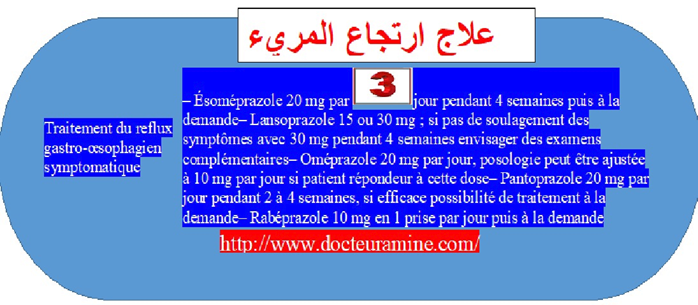

. تتمثل الأعراض كأول خطوة السريرية في الحرقان، الارتجاع، السائل الحمضي في الفم) .و بدون الإصابة بالتهاب المريء . ما يتم اقتراح قواعد التغذية والنظافة (19) كأول خطوة بالنسبة للأشكال الأقل شدة. وفي حالة الإخفاق أو الأعراض الأكثر شدة يتم اقتراح أدوية م م ب مثل ما توصف مضادات الحمض الألجينية (20) يستخدم حمض الألجنيك، بشكل خاص في طب الأسنان وصناعة الغراء (21) ، أو مضادات ه2 (22) في حالة غياب انجاز الفحوص الإضافية حينما لا يعاني المصاب من علامة التخدير (23)(العمر أقل من 50 سنة و عدم نقص وزن الجسم بجانب عدم تدهور الحالة الصحية و عدم بروز علاقة النزيف الهضمي و عدم الإصابة بسوء البلع و عدم الإصابة بسوء البلع (24) .

يتحتم أن يتم التقييم 4 أسابيع من العلاج حينما يبرز المصاب أعراض سريرية بالرغم من تناول م م ب ، فيمسي اقتراح الفحوص الإضافية أمرا قائما. لتأكيد أو عدم تأكيد وجود حالة ا م ب والبحث عن سبب آخر الأعراض السريرية بالرغم من تناوله م م ب يمسي الاستمرار في متابعة العلاج بأدنى جرعة فعالة محتملة، يصبح أمرا قائما يطرح فوق طاولة المناقشة. و حينما تنتكس الأعراض النمطية بعد إيقاف العلاج، فينصح التالي باللجوء لإنجاز فحوص إضافية للتأكيد من وجود ا م م .

لا ينصح بتناول الأدوية المضادة للحموضة قصد تخفيف الأعراض الغير منهجية المنفردة (25) المحتملة مرتبطة بالارتجاع المعدي المريئي (أعراض الأنف والأذن والحنجرة، السعال المزمن، الربو المزمن: ألم الصدر الغير ناجمة عن أمراض القلب) في غياب الفحوص الإضافية التي توثق الارتجاع المريئي. لذلك من ناحية أخرى، يجب استكشاف المرضى الذين يعانون من أعراض غير نمطية. يحتمل أن تلج طيف ارتجاع المريء (26) . يجب استكشافهم قبل تسليم أية وصفة أدوية م م ب للتأكد من صحة الأعراض الناجمة فعلا عن تناول م م ب .